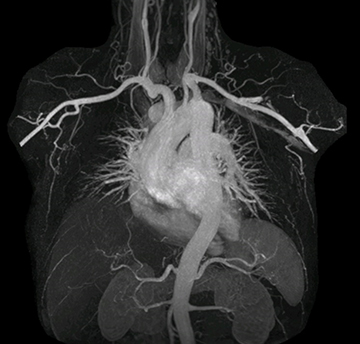

The subtractionless peripheral MR angiography shows improved vessel-to-background contrast and high resolution. Ingenia Ambition 1.5T.

| Station | Ingenia Ambition |

| Pelvis | Voxels 1.3 x 1.3 x 3.2 mm, FOV 430 mm, 125 slices |

| Upper legs | Voxels 1.3 x 1.3 x 3.2 mm, FOV 430 mm, 125 slices |

| Lower legs | Voxels 1.0 x 0.82 x 2.0 mm, FOV 430 mm, 125 slices |

“In MRA, the capacity to acquire a sequence in a single breathhold provides images that are motion-free and high in contrast and detail, advantages that aid in diagnosis,” he says. “With Compressed SENSE, we can reduce the time for the single breath-hold to just 2-3 seconds. Before Ingenia Ambition and Compressed SENSE, the breath-hold requirement was about 8 to 9 seconds, which was too long for some patients.”

“In our peripheral MRA run-off studies with Ambition we realize key benefits, including outstanding image quality and significantly reduced breath-hold and scan times, which not only benefit the patient, but also provide the opportunity to add sequences that could aid in diagnosis,” Dr. Peña says.

“Before we had Ingenia Ambition, our CE-MRA run-off studies would first acquire a dynamic pre-contrast scan with 20-25-second breath-holds, then inject the contrast, do another acquisition and then subtract the two,” says Avila. “Now, mDIXON XD allows us to complete the study in just one single pass – without need for a pre-exam – which eliminates subtraction artifacts and almost halves the scan time. In addition, mDIXON provides much better background suppression, which really improves vesselto-background contrast. And, thanks to Compressed SENSE, the single breath-hold is not long and we improve image resolution.”